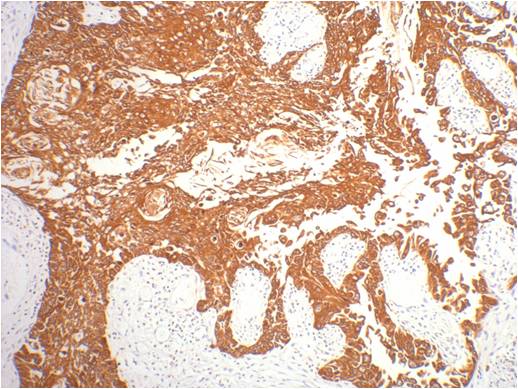

Product name: CK16 Mouse mAb

Background: Keratin 16 is expressed in keratinocytes, which are undergoing rapid turnover in the suprabasal region (also known as hyperproliferation-related keratins). Keratin 16 is absent in normal breast tissue and in noninvasive breast carcinomas. Only 10% of the invasive breast carcinomas show diffuse or focal positivity. Reportedly, a relatively high concordance was found between the carcinomas immunostaining with the basal cell and the hyperproliferation-related keratins, but not between these markers and the proliferation marker Ki-67. This supports the conclusion that basal cells in breast cancer may show extensive proliferation, and that absence of Ki-67 staining does not mean that (tumor) cells are not proliferating.